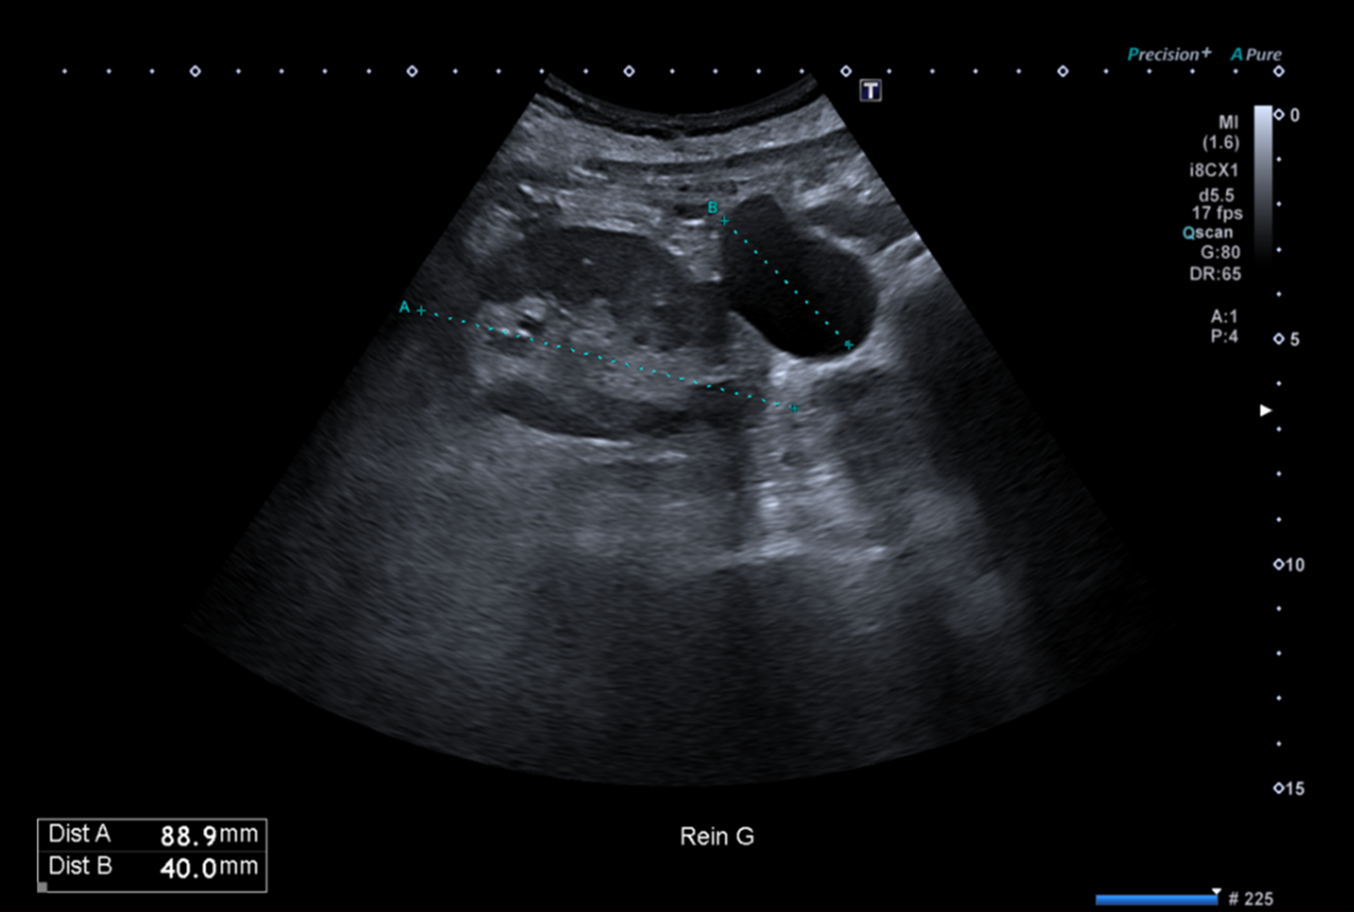

Pour illustrer cela, à quoi vous fait penser cette formation anéchogène située au pôle inférieur du rein gauche sur cette coupe d’échographie abdominale réalisée dans un contexte de surveillance de cirrhose post infection VHC chez une patiente de 74 ans ?

Celui qui se contente de cette seule coupe répondra très probablement kyste simple.

Celui qui aura balayé entièrement l’organe et son environnement, et qui aura complété son examen par le doppler couleur répondra différemment.